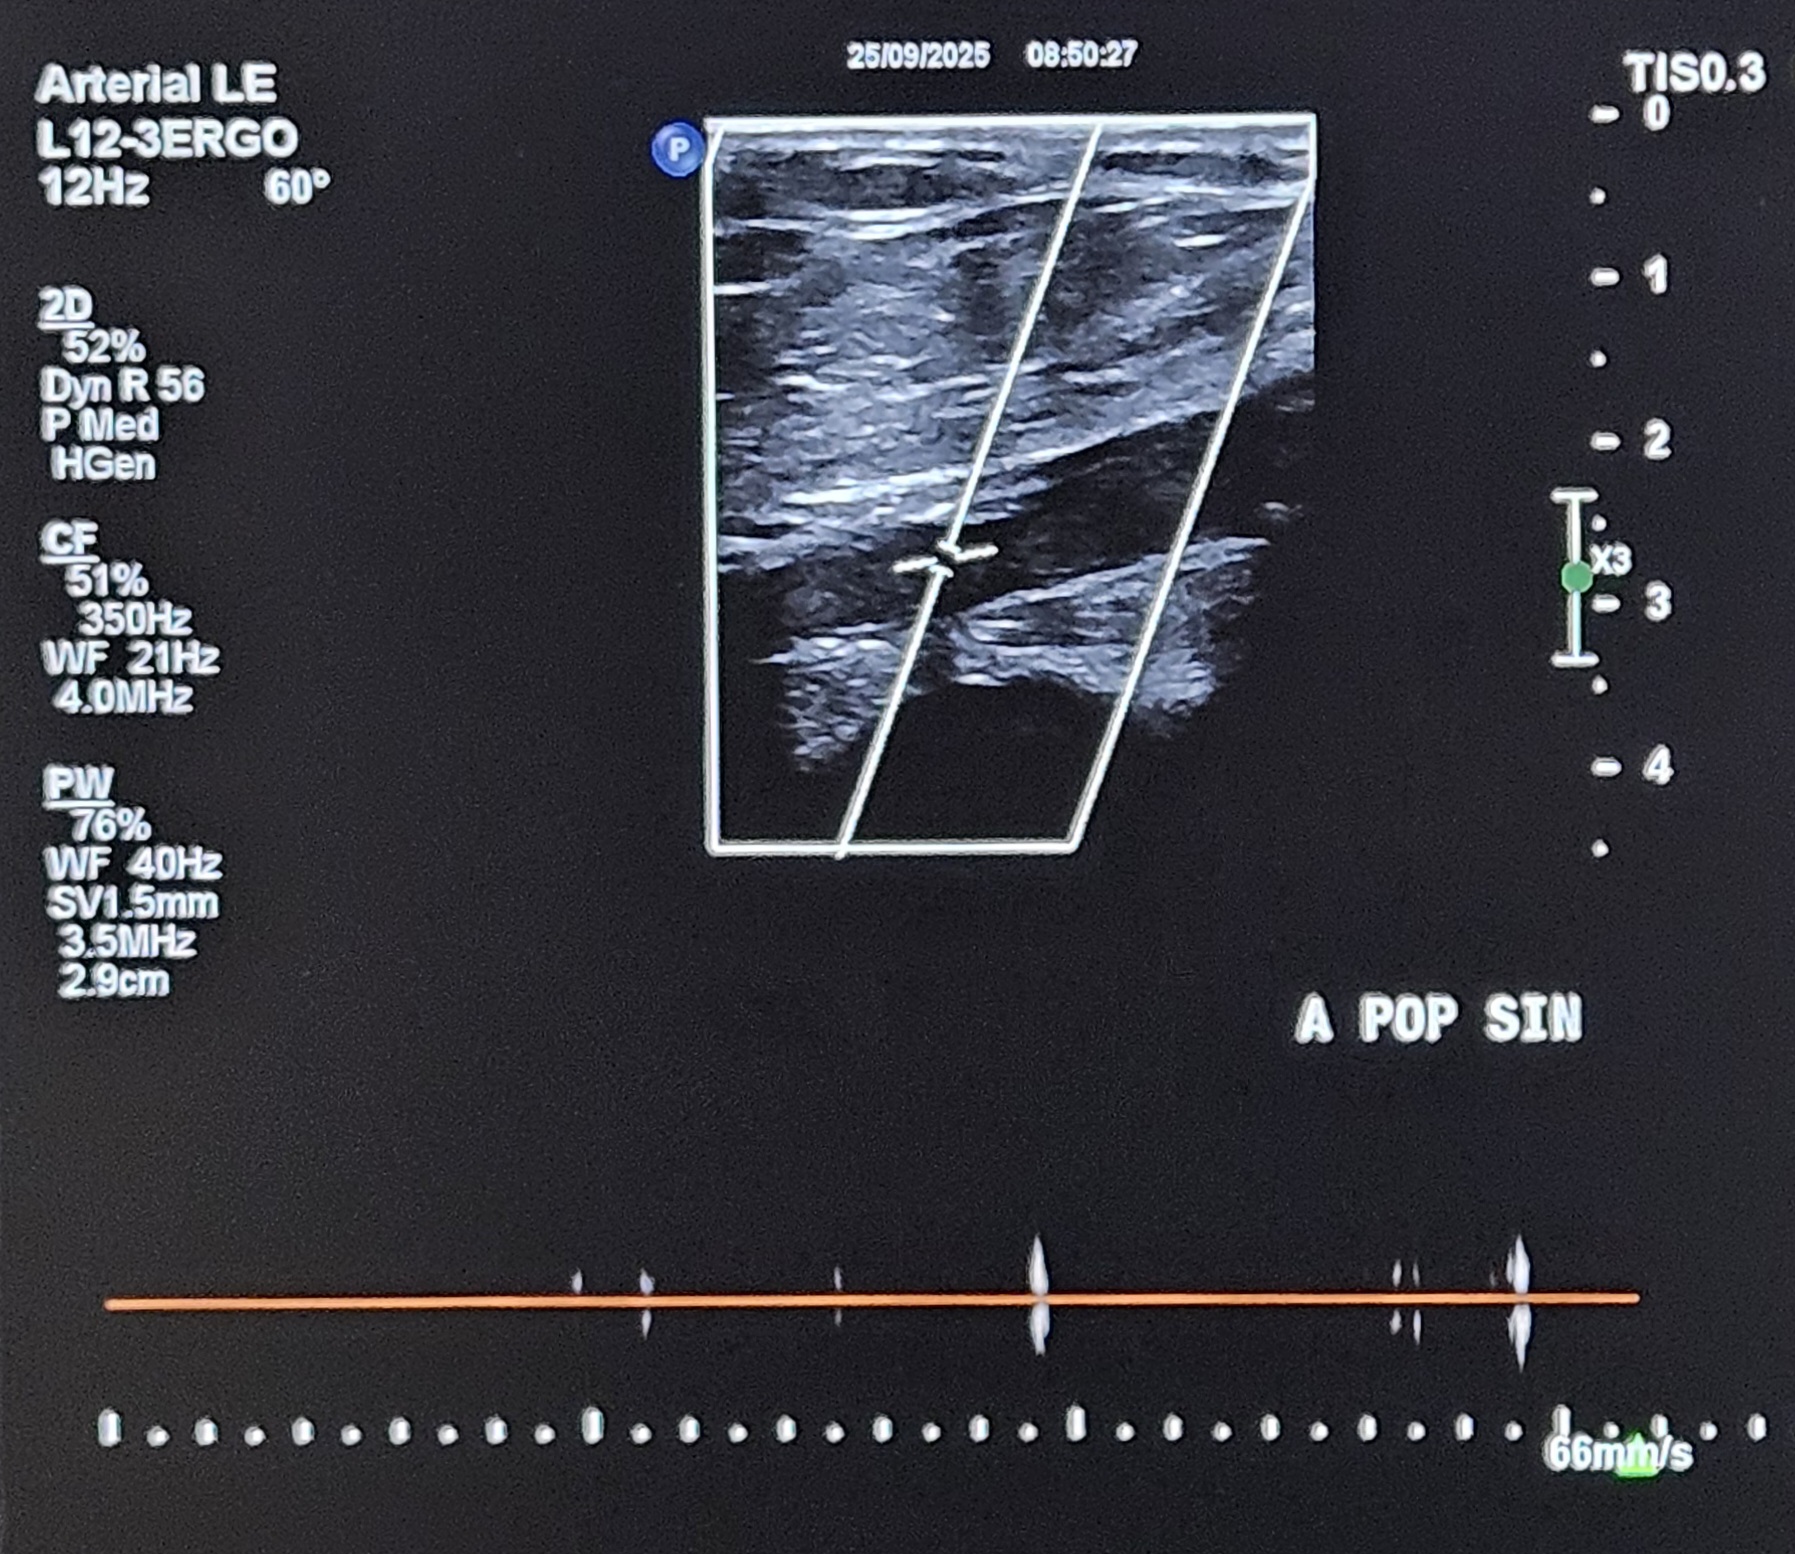

Relevant Test Results Prior to Catheterization

Doppler ultrasound demonstrated triphasic waveform at the left common femoral artery and biphasic flow at the mid superficial femoral artery (SFA). There was total occlusion from the distal SFA to the distal popliteal artery, with monophasic high end-diastolic flow at the anterior tibial artery (ATA), consistent with severe infra-popliteal ischemia.